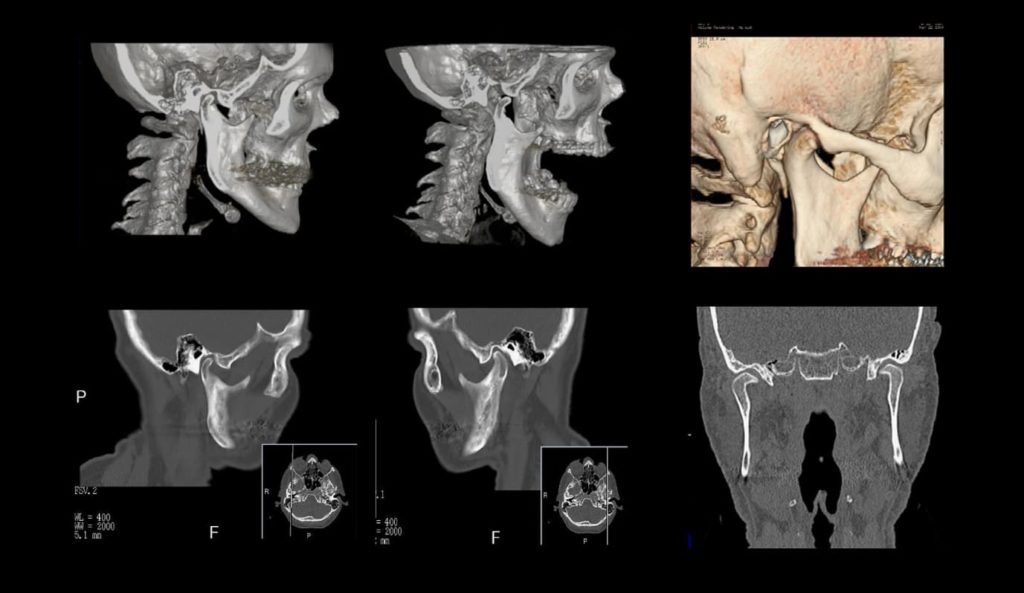

Что видно на снимках КТ ВНЧС

Сканы компьютерной томографии получаются в черно-белой цветовой гамме, но это не мешает различать ткани разной плотности. Отличающиеся по составу волокна отражаются на снимках разными оттенками серого. Благодаря этому заметны четкие границы между отдельными элементами височно-нижнечелюстного сустава:

- головкой нижней челюсти;

- суставным диском;

- суставным бугорком;

- синовиальной капсулой;

- связочным аппаратом.

В особом режиме сканирования можно различить мышечную ткань, но при изучении сустава это не всегда необходимо. Хрящи видны хуже, но увидеть их границы, косвенно измерить толщину тоже возможно (по расстоянию между костями).

В дифференциальных режимах компьютерной томографии хорошо различимы следующие патологии:

- изменение структуры и плотности костей височно-нижнечелюстной зоны;

- деформация формы и ширины суставной щели;

- дистрофия суставного диска;

- нарушения в структуре и толщине жевательной мускулатуры;

- внутренние кровоизлияния в суставной капсуле, разрастание гематомы;

- смещение суставных головок в расслабленном состоянии;

- увеличение в размерах или стирание суставных поверхностей;

- новообразования костей, опухоли сопредельных мягких тканей.

Если пациент перенес травму лицевой части черепа, на сканах хорошо видны трещины, переломы, костные отломки. Компьютерная томография нередко становится методом выбора в исследовании суставных сосудов. Их разрывы, расслоение стенок и прочие повреждения четко просматриваются на снимках.